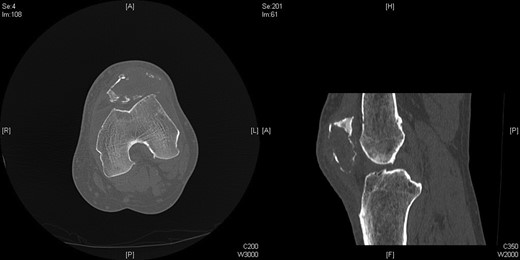

Nineteen months earlier the patient had consulted his general practitioner complaining of left knee pain. Radiographs performed at that time were reported to show joint space narrowing within the patello-femoral compartment as well as early joint space narrowing within the medial compartment. A subchondral lucency was also noted within the patella which was described as a subarticular cyst secondary to the previously mentioned patello-femoral degeneration (Figs 1–3).

Repeat radiographs performed by his general practitioner 19 months after initial presentation (Figs 4–6) revealed a large lucency within the patella and a discontinuity in the anterior cortex of the inferior pole suggesting pathological fracture. A bone scan was arranged and demonstrated isolated abnormal tracer activity around the left patella (Fig. 7). Due to the pacemaker a computed tomography (CT) scan was performed to further characterize the lesion. This confirmed a large lucent area occupying most of the patella with multiple areas of cortical disruption along its anterior border (Fig. 8). Since the exact nature of the lesion could not be determined an ultrasound-guided biopsy was suggested but ultrasound screening revealed the lesion to be highly vascular (Fig. 9). In view of this the radiologist performed a renal ultrasound, which revealed a large mass arising from the superior pole of the left kidney. Subsequent CT of the chest, abdomen and pelvis followed demonstrating the extent of disease. There was a large (13 × 8.5 × 9 cm) mass arising from the superior pole of the left kidney (Fig. 10), the appearances of which were consistent with a primary RCC. Metastases were found in both adrenals and lungs, but no other bone metastases. Since diagnosis, the patient has had a left nephrectomy and is currently receiving radiotherapy and zolendronic acid treatment for the patella metastasis. At the time of writing this report the patient's patella lesion continues to be managed non-operatively.

The absence of associated features of systemic disease, as well as radiographic appearances in keeping with early patello-femoral osteoarthritis (OA), account for the delay in diagnosis. The initial images suggest mild degeneration but, whilst subarticular cysts are a radiographic feature of OA, the lesion shown in this case is larger than would be expected with the level of disease shown elsewhere in the joint.